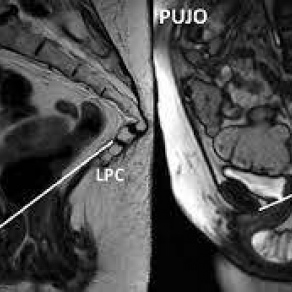

Resonancia nuclear magnetica dinamica de piso pelvico. EN. Codigo 883441 (2022)